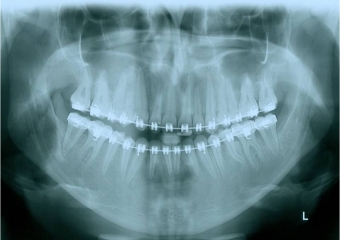

Raio x panorâmico inicial - Clínica Cliniface

Raio x panorâmico inicial